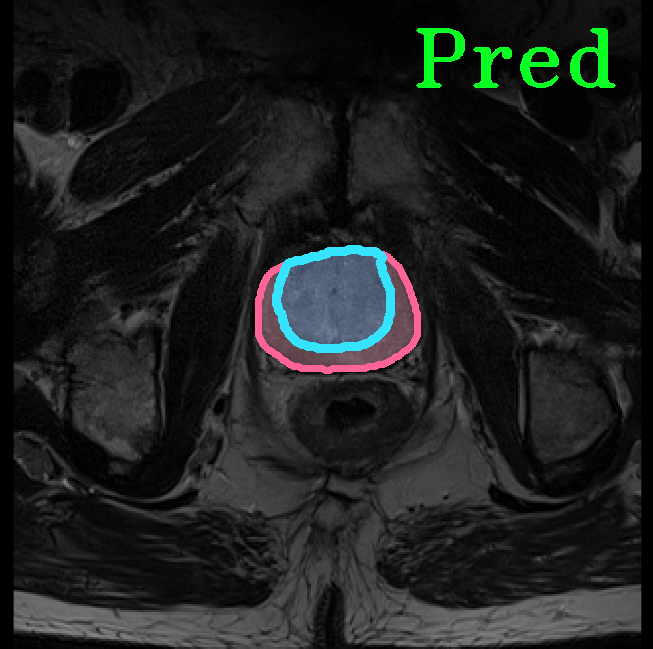

TransFuse is evaluated on both 2D and 3D datasets to demonstrate the effectiveness. As different medical image segmentation tasks serve different diagnosis or operative purposes, we follow the commonly used evaluation metrics for each of the segmentation tasks to quantitatively analyze the results. Selected visualization results of TransFuse-S are shown in Fig. 2.

Results of Prostate Segmentation. We compare TransFuse-S with nnU-Net [12], which ranked 1st in the prostate segmentation challenge [22]. We follow the same preprocessing, training as well as evaluation schemes of the publicly available nnU-Net framework333https://github.com/MIC-DKFZ/nnUNet and report the 5-fold cross validation results in Tab. 6. We can find that TransFuse-S surpasses nnUNet-2d by a large margin (+4.2%) in terms of the mean dice score. Compared to nnUNet-3d, TransFuse-S not only achieves better performance, but also reduces the number of parameters by 41% and increases the throughput by 50% (on GTX1080).

| Prostate Segmentation | |||

|

|

|

|